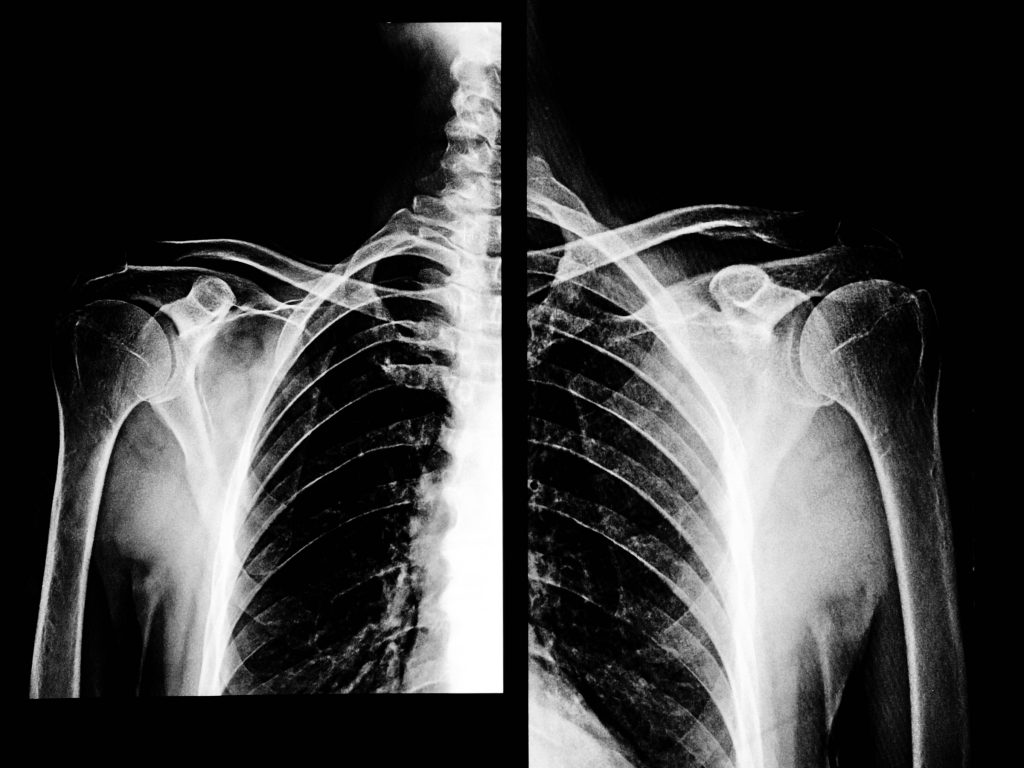

But data shows improvements can be made with simple changes. Also, a patient’s emotional state often impacts on their symptoms. So, I helped develop a campaign for people to use an app to measure their ‘lung age’. The app also tracks physical activity and emotional wellbeing. Plus it provides helpful tips for people diagnosed.

The Lung Life app is a tool for people with COPD to manage their disease and it gives doctors insights into individual patients, to tailor treatment. By using insights with empathy and creativity I told the story of how small changes can have a big impact. Helping two different parties with a common goal and improving outcomes for all.